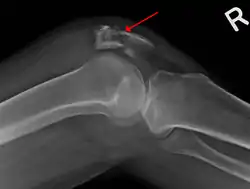

![]() كسر في الرضفة من منظور جانبي كسر في الرضفة من منظور جانبي | |

عادةً ما يُنتج عن ضربة قوية في الجزء الأمامي من الركبة أو السقوط على الركبة.[1] في بعض الأحيان قد يحدث من تقلص قوي في عضلات الفخذ.[1] يغتمد التشخيص على الأعراض ويُأكد مع الأشعة السينية.[3] عند الأطفال قد يتطلب التصوير بالرنين المغناطيسي.[3]

يستند التشخيص على الأعراض ويُأكّد بالأشعة السينية،[3] قد يتطلب التصوير بالرنين المغناطيسي عند الأطفال.[3]